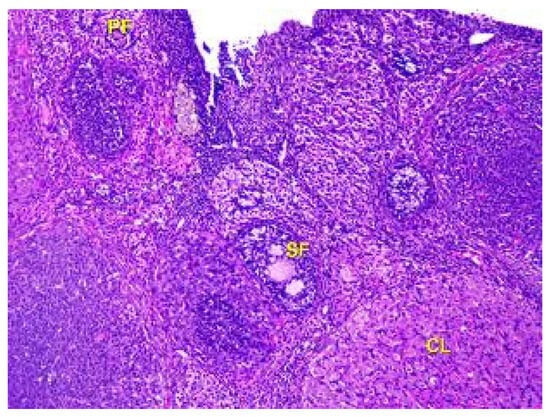

- Denefil, O.V.; Bilyk, Y.O.; Chorniy, S.V.; Fedoniuk, L.Y.; Chornii, N.V. The peculiarities of morpological changes of rats’ ovary and biochemical state under the damage with different doses of lead acetate. Wiad Lek. 2022, 75, 377–382. [Google Scholar] [CrossRef] [PubMed]